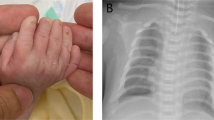

Ellis–van Creveld syndrome (EVC) is a relatively rare, usually non-lethal, autosomal recessive skeletal dysplasia characterized by short stature, polydactyly, cardiac and renal anomalies. Linkage analysis has localized the disease gene to chromosome 4p16, with the markers at loci D4S827 and D4S3135 defining the centromeric and telomeric limits of the linked interval, respectively. There has been long-term speculation that asphyxiating thoracic dystrophy (ATD) and the short-rib polydactyly syndromes (SRP) represent the severe end of the EVC disease spectrum. We performed linkage analysis using markers from the EVC region in seven families manifesting either ATD or SRP type III. In two of the families, one segregating ATD and one SRP kindred, linkage of the phenotype to the EVC region was excluded. In the other five families linkage of the phenotype to the EVC region could not be excluded, but the families were too small for linkage to the region to be established. The exclusion of the EVC region in ATD and SRP III families suggests that locus heterogeneity exists within the short-rib dysplasia (with and without polydactyly) group of disorders.